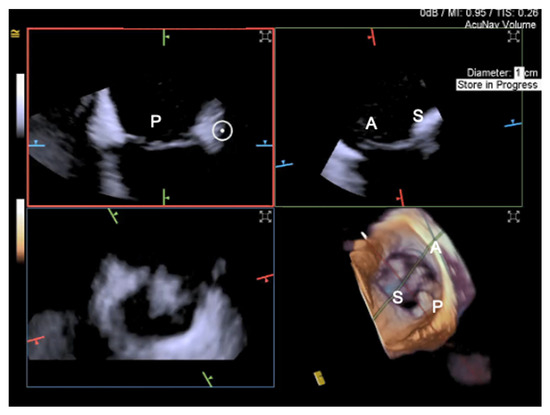

3.2. Intracardiac Echocardiography: Strenghts and Limitations

3.3. Fluoroscopy